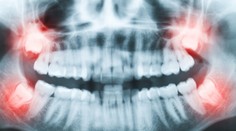

Vypadávanie zubov môže mať aj inú príčinu. Vedci totiž odhalili významnú súvislosť Róbert Ďurkáč 12. 8. 2024

Zdravie Zubári prezradili najhoršie zlozvyky, ktoré ničia zuby a ďasná a robí ich takmer každý Katarína Kiššová 16. 7. 2024

Zdravie Deväť vecí, ktoré by dentista svojim zubom nikdy neurobil. A nemali by ste ani vy Ľubomíra Ivanková 19. 11. 2023

Zdravie Zubári vybrali šesť najškodlivejších potravín a nápojov, ktoré ničia ústnu hygienu a kvalitu zubov Katarína Kiššová 25. 6. 2023